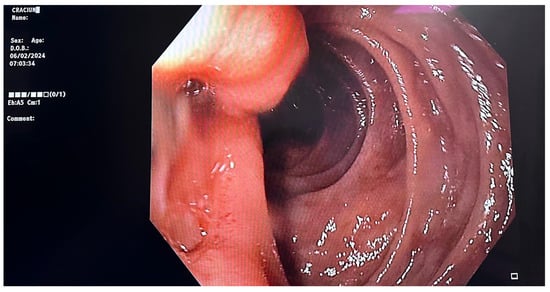

2. Detailed Case Description

2.1. Diagnostic Evaluation